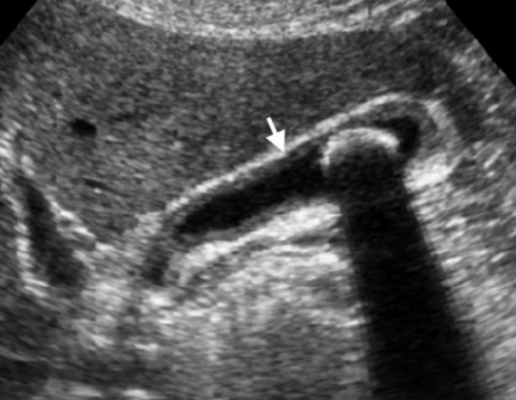

Представлен больной с хроническими болями в правом подреберье, который ежедневно воздерживался от еды с вечера. Утолщение слабо выраженное и не является физиологическим. Также визуализируются обструкция и камень. После УЗИ данному больному был поставлен диагноз — хронический холецистит.